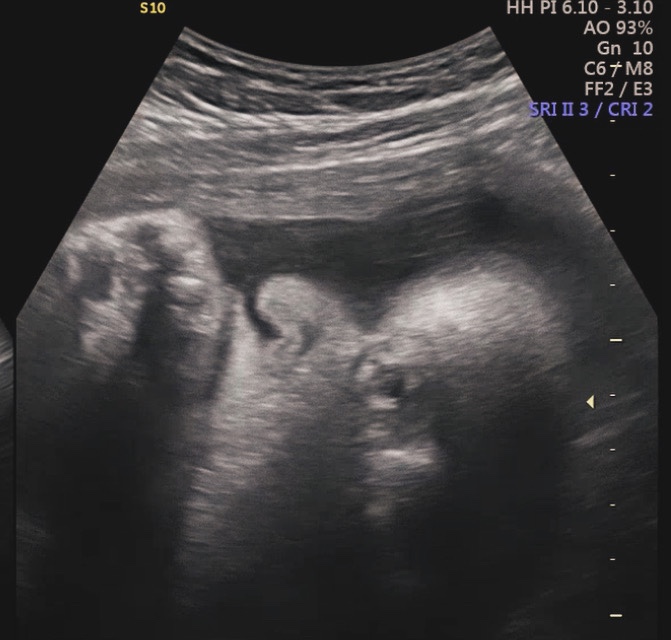

스펙타클한 38주 자연분만 과정! 인천 더블유여성병원 유도분만 후기

우리 아기 55일차! 낮잠자는 시간에 후딱 써보는 스펙타클한 자연분만 출산후기! 인천 더블유여성병원에서 ...